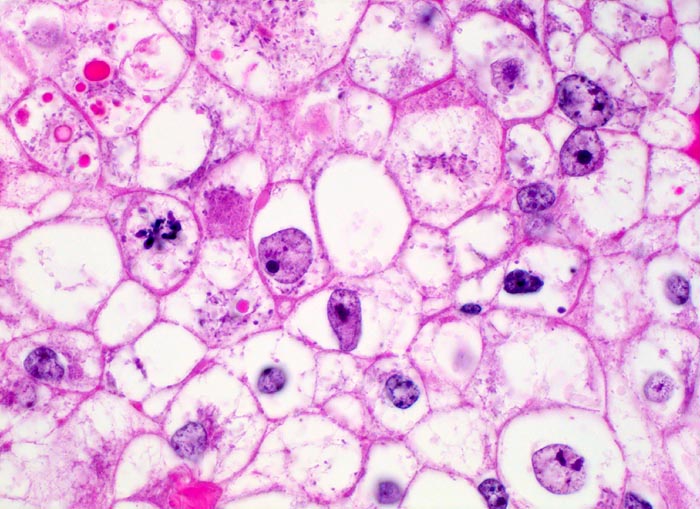

PathoPic – image database / PathoPic ID 4892 - mässig differenziertes hellzelliges Nierenzellkarzinom

mässig differenziertes hellzelliges Nierenzellkarzinom

Klarzelliger Tumor mit deutlichen Zellgrenzen. Das reichlich vorhandene Zytoplasma ist entweder klar oder fein granuliert. Ein Teil der Tumorzellen enthält rote intrazytoplasmatische hyaline Globuli. Mitose.

Hyaline Globuli können oft bei Nierenzellkarzinomen beobachtet werden. Sie kommen aber auch in vielen anderen Tumoren (Bsp. Hepatozelluläres Karzinom, Dottersacktumor) und in gutartigen Veränderungen vor. Die genaue Ätiologie und Bedeutung der Einschlüsse ist nicht geklärt.